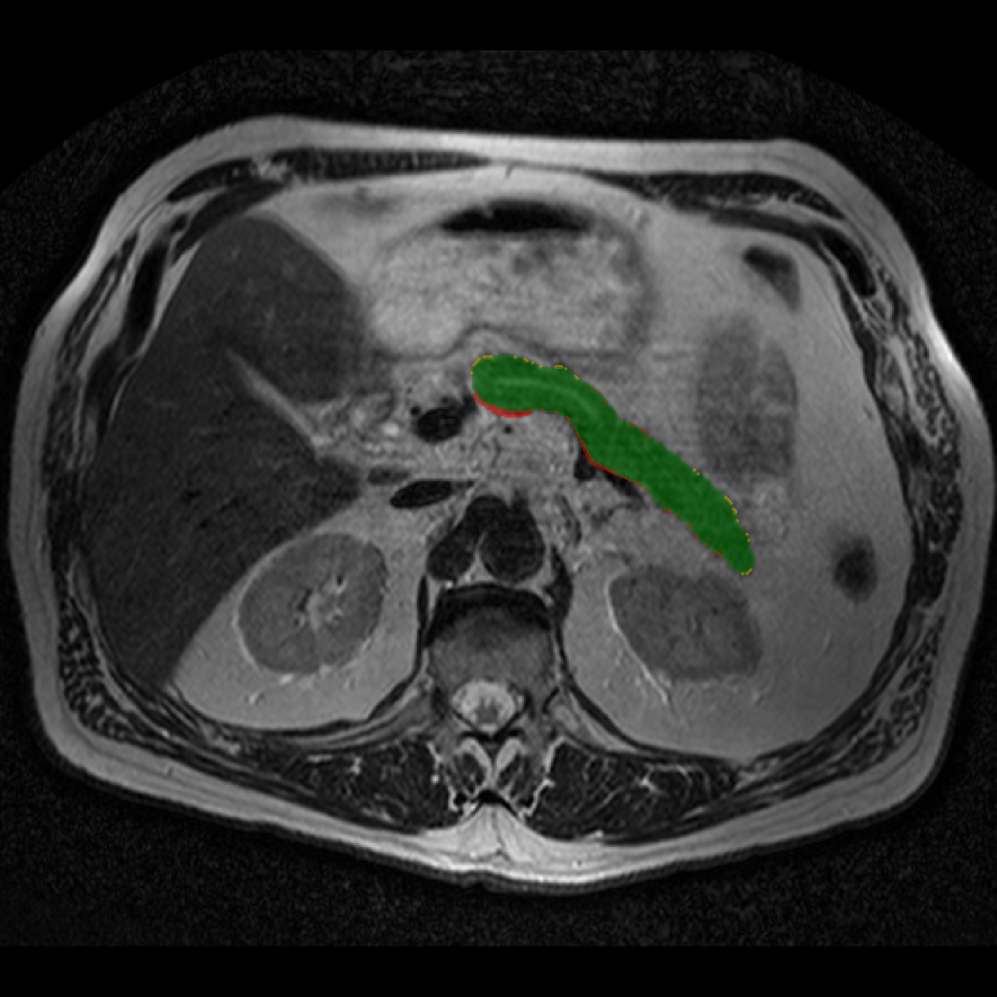

Accurate pancreas segmentation is a critical prerequisite for precise cyst analysis and classification. Recently, we developed PanSegNet [zhang2025large], a novel segmentation architecture incorporating linear self-attention layers [zhang2022dynamic] within the nnUNet framework [isensee2021nnu] to enhance global information modeling capabilities while maintaining computational efficiency (Fig. 1). PanSegNet demonstrated exceptional segmentation performance across both T1W and T2W modalities, achieving mean dice scores of 86.817.30% and 89.626.38%, respectively (Table 1, Fig. 2b-c). This performance significantly exceeded that of Swin-UNETR [hatamizadeh2021swin], one of the most used state-of-the-art transformer-based medical segmentation models, which achieved dice scores of 79.091.40% and 76.290.66% for T1W and T2W, respectively (). In this study, we integrated PanSegNet into our Cyst-X engine along with a classifier for risk prediction. In Section 2.2, we show that the choice of segmentation model affects the classification results. The performance advantage of PanSegNet was consistent across all seven medical centers, demonstrating robust generalization despite variations in imaging protocols and equipment (Table 1). This cross-institutional reliability is particularly important for clinical applications, where model performance must remain consistent regardless of imaging site or acquisition parameters.

Each patient was categorized into one of these three ground truth classes: no risk/control, IPMN low-risk, or IPMN high-risk. To evaluate variability in image acquisition, we applied uniform manifold approximation and projection (UMAP) to image quality indicators, revealing distinct clustering patterns by imaging center and slice thickness. This heterogeneity reflects real-world clinical variability, enhancing the dataset’s generalizability while presenting technical challenges for model development. Fig. 6 shows examples of low-grade, high-grade, and cancer developing IPMNs from the Cyst-X dataset.